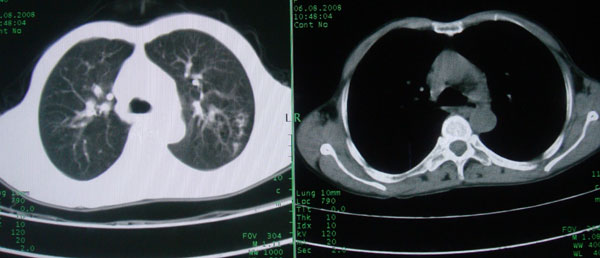

考虑支气管扩张并感染

1慢支伴感染;右下肺周围型肺癌。

1\\慢支并感染

2\\浸润型肺结核

本例应该是“慢性疾病并发多种合并症”即:慢支并感染并支气管扩张征!结合病灶分布 形态分析,不除外合并“继发性肺结核”!